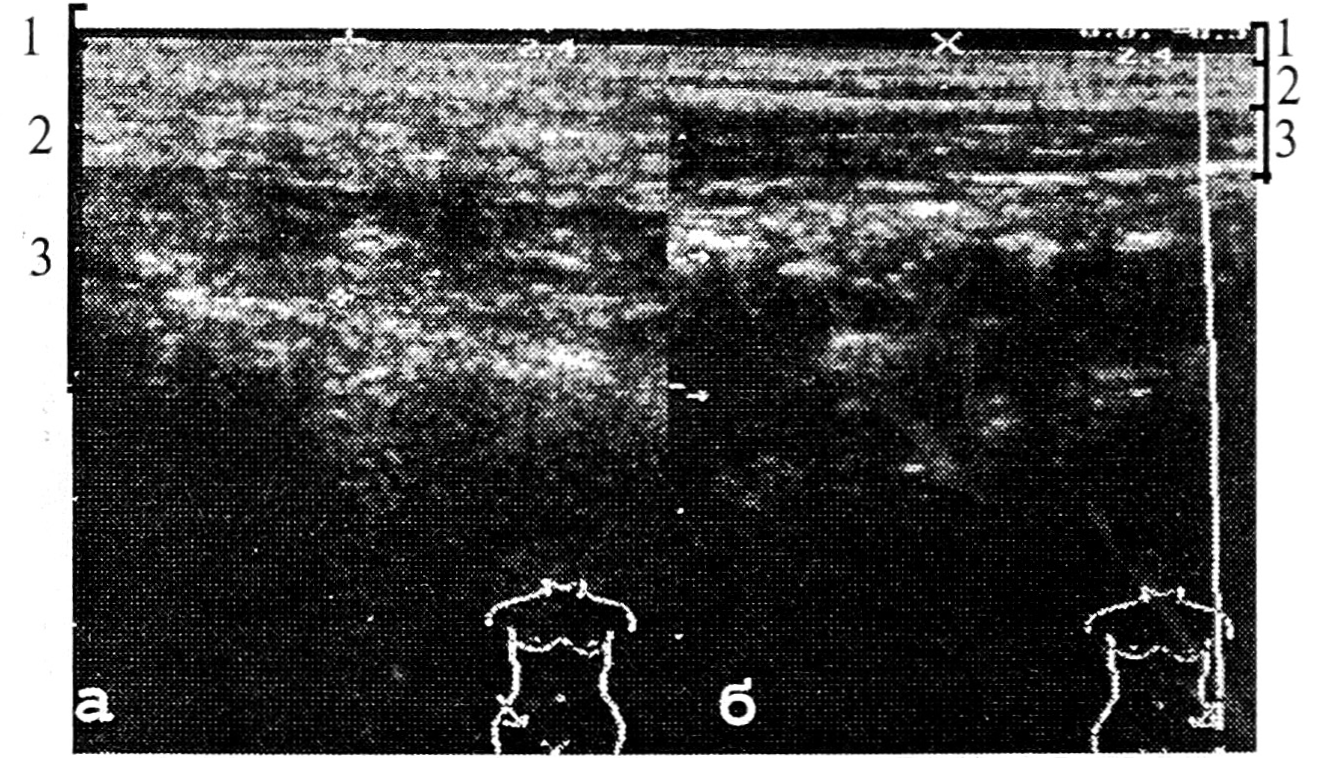

При исследовании инфильтрата определялся участок подкожной жировой клетчатки и мышц, отличающийся по плотности от окружающих тканей. По структуре этот участок был эхонеоднороден, то есть более плотные участки чередовались с менее плотными; отмечалась смазанность структуры по сравнению с более четкой структурой окружающих тканей. В отличие от гнойников, не было участков, свободных от эхосигналов (рис. 10).

Рис. 10. Сонограммы воспалительного инфильтрата послеоперационной раны: а — на стороне послеоперационного рубца; б — интактная сторона.